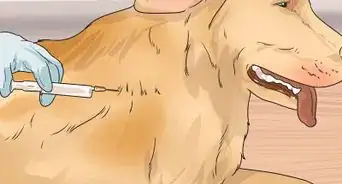

- Always take your dog to the vet if you suspect pregnancy, as they can do an ultrasound or run a blood test to confirm or deny pregnancy.

Veterinarian An ultrasound scan can detect pups from around 21 days, while a blood test from 28 days can confirm pregnancy. Often the earliest physical sign of pregnancy is 'pinking up,' when the dog's nipples become swollen, pink, and more noticeable.

An ultrasound scan can detect pups from around 21 days, while a blood test from 28 days can confirm pregnancy. Often the earliest physical sign of pregnancy is 'pinking up,' when the dog's nipples become swollen, pink, and more noticeable.